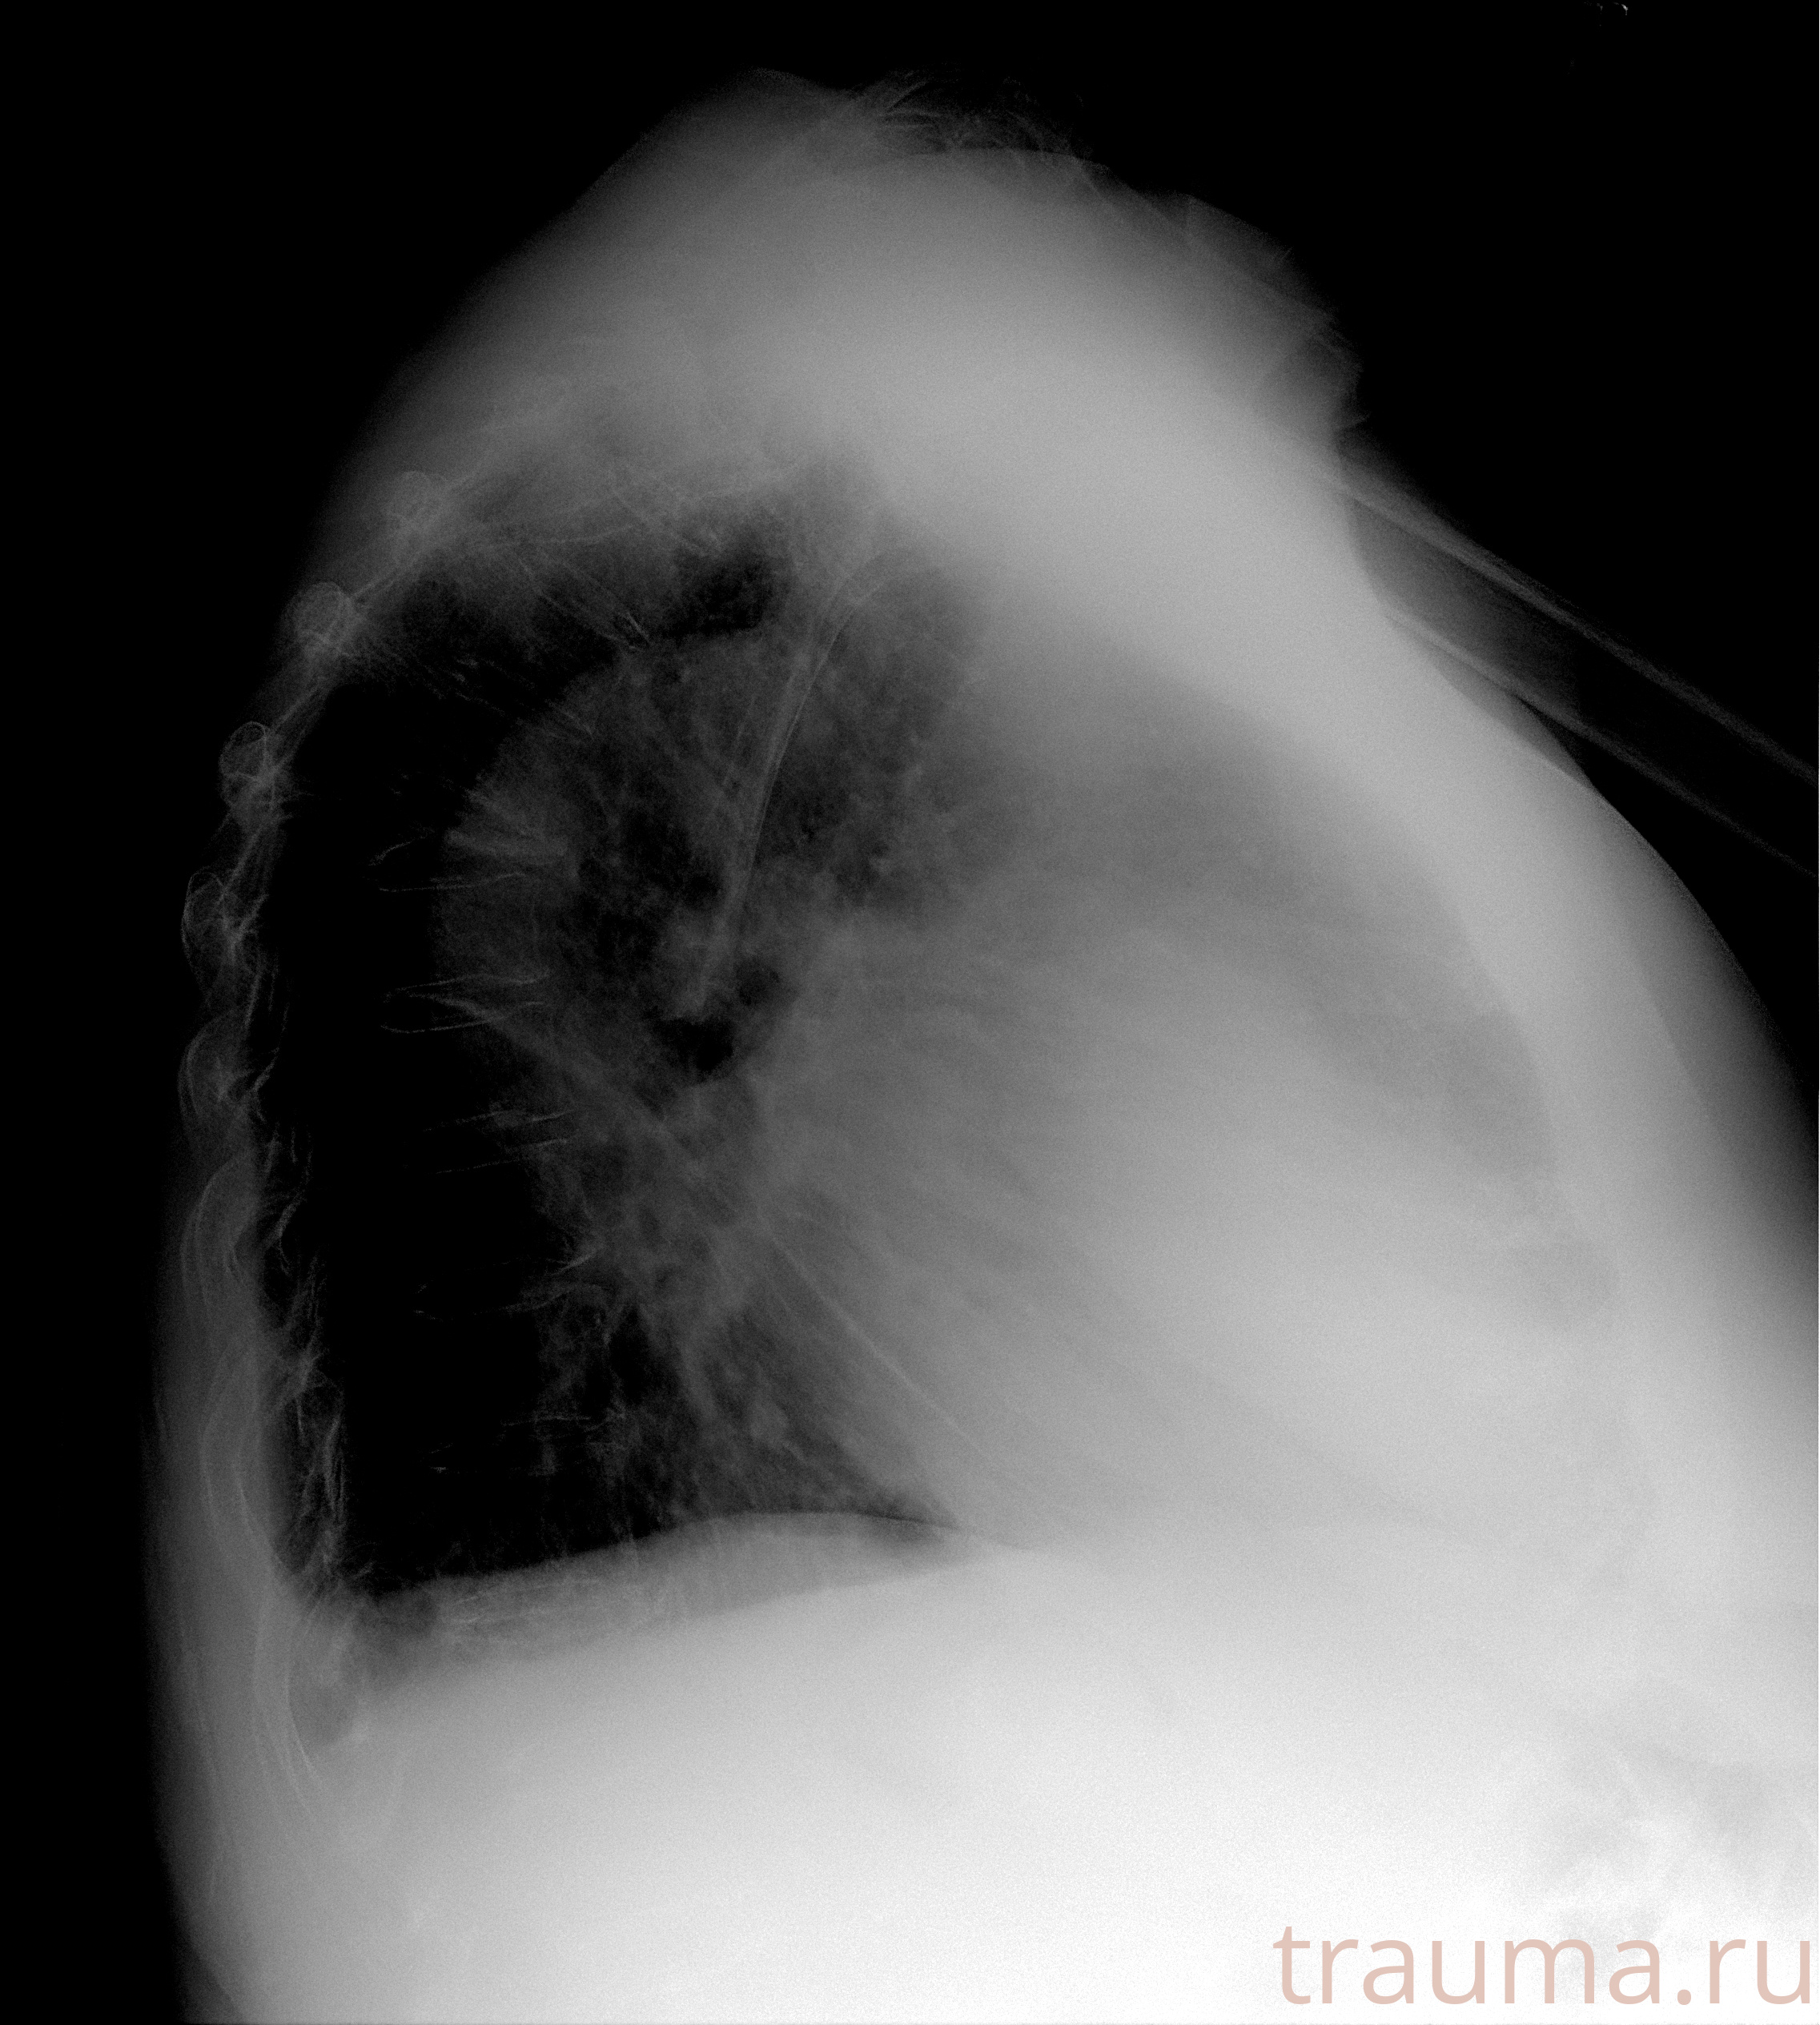

Рентген на дому: по вашему адресу приезжает врач-рентгенолог, травматолог-ортопед с мобильным рентгеновским аппаратом, проводит диагностику травмы или заболевания, делает необходимые рентгенограммы, дает рекомендации по дальнейшему лечению. Получить качественные снимки в домашних условиях возможно благодаря уникальной методике, разработанной МосРентген Центром для института  Склифосовского

при переломе шейки бедра и пневмонии от компании МосРентген Центр - партнера Института имени Склифосовского